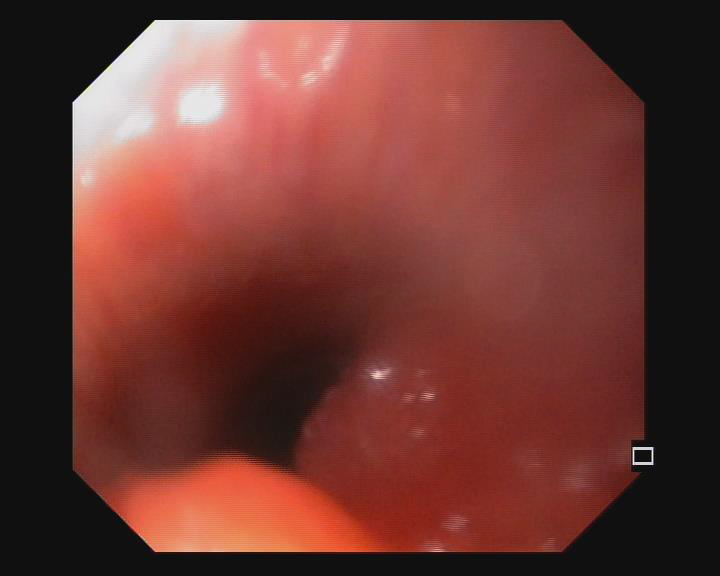

Fig 4: Bronchoscopic image of tracheal infiltration